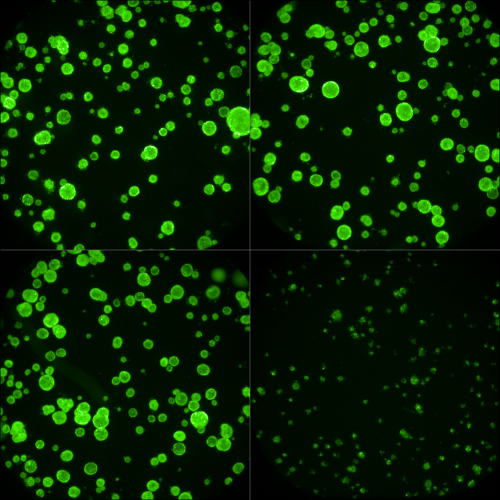

Researchers at UMC Utrecht have made significant advances in the treatment of metastatic colorectal cancer. Three new studies show that so-called organoids – small, laboratory-grown versions of a patient’s tumor –are valuable predictors of treatment response while also providing new insights into therapy resistance.

Physician-researcher Lidwien Smabers explains how the approach works: “We take a small piece of tumor tissue from a patient, from which we grow mini-tumors , called organoids. We then test standard treatments on these organoids to evaluate their value in predicting patient response to chemotherapy and targeted therapies.”

UMC Utrecht has now established a biobank of more than 500 colorectal cancer organoids, enabling researchers to match future patients with organoids that most closely resemble their tumor. “This means we don’t have to create a new mini-tumor for every patient”, Roodhart explains. “We can test in the lab whether a treatment is likely to be effective before administering it to the patient.”

organoids